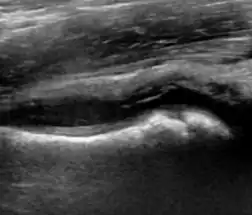

Ultrasound

Ultrasound is the first-choice technique for diagnosis of newborns hip dysplasia. In experienced hands with appropriate technology, ultrasound can also be useful during the first year of life. Some European healthcare systems encourage universal ultrasound screening in neonates between the sixth and eighth weeks. Although it shows higher initial costs caused, it leads to significant reduction in the total number and overall costs of dysplastic hips undergoing operative and nonoperative treatment.[1]

Ultrasound allows categorizing pediatric hips, according to Graf’s criteria, in four main types: normal, immature, and dysplastic (subluxed and dislocated). This classification is based on measurements of the acetabular inclination angle (alpha), cartilage roof angle (beta), and infant age. The femoral head coverage can also be determined by dividing the length of the femoral head covered by the acetabular fossa and the diameter of the femoral head. Its lower normal limits are 47% for boys and 44% for girls (Figure 11).[1]

Figure 11:

-

Useful ultrasound measures in neonatal hip sonography, alpha and beta angles.[1] -

Measurement of femoral head coverage.[1]